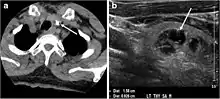

Nodules in skin include dermatofibroma[5] and pyogenic granuloma.[6] Nodules may form on tendons and muscles in response to injury,[7] and are frequently found on vocal cords.[8] They may occur in organs such as the lung,[9] or thyroid,[10] or be a sign in other medical conditions such as rheumatoid arthritis.[11]

Often discovered unintentionally on a chest x-ray, a single nodule in the lung requires assessment to exclude cancer.[9]

- 1 2 Britton, K. E.; Gilday, David L.; Maisey, Michael (2013-12-11). Clinical Nuclear Medicine. Springer. ISBN 978-1-4899-3358-4.